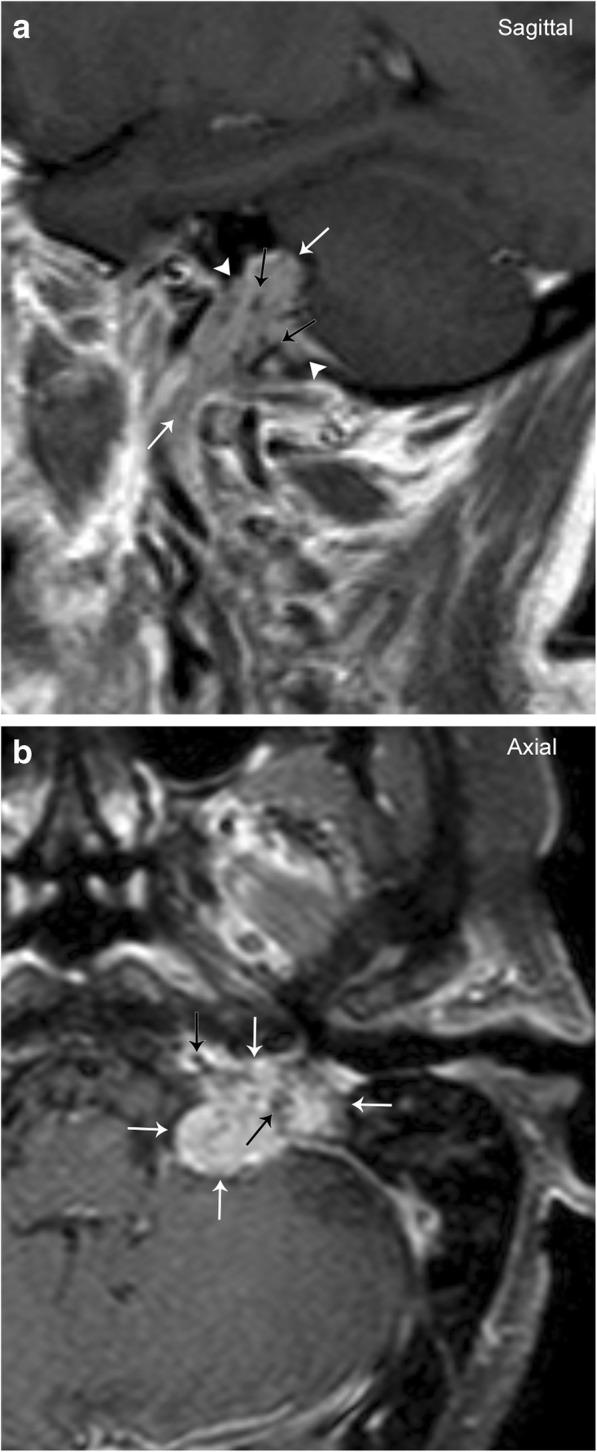

The complex anatomy of the carotid space within a small confined area is unique to the head and neck and allows for a vast array of pathology. This paper will review the anatomy of the carotid space from the skull base to the thorax, defining its borders at multiple levels, as well as its contents. The paper will also describe the myriad of mass lesions and vascular pathologies that may occur within the carotid space. The discussion will include anatomic considerations in differential diagnoses, imaging features, and lesion characteristics across multiple imaging modalities including CT, MRI, ultrasound, and conventional angiography. Entities discussed include paragangliomas, nerve sheath tumors, meningioma, fibromuscular dysplasia, carotidynia, thrombus, dissection, pseudoaneurysm, and pathology of the deep cervical chain lymph nodes. Understanding the complex and unique anatomy of the carotid space, as well as the nuances of navigating a broad differential, will empower the reader to make an accurate diagnosis.

在狭小受限区域内,颈动脉间隙复杂的解剖结构是头颈部所特有的,且会引发大量病变。本文将回顾从颅底到胸部的颈动脉间隙解剖结构,界定其在多个层面的边界及其内容物。本文还将描述可能出现在颈动脉间隙内的众多肿块性病变和血管病变。讨论将包括鉴别诊断中的解剖学考量、多种成像方式(包括CT、MRI、超声和传统血管造影)的成像特征及病变特点。所讨论的疾病包括副神经节瘤、神经鞘瘤、脑膜瘤、纤维肌发育不良、颈动脉痛、血栓、夹层、假性动脉瘤以及颈深链淋巴结病变。了解颈动脉间隙复杂独特的解剖结构以及鉴别广泛病变的细微差别,将使读者能够做出准确诊断。